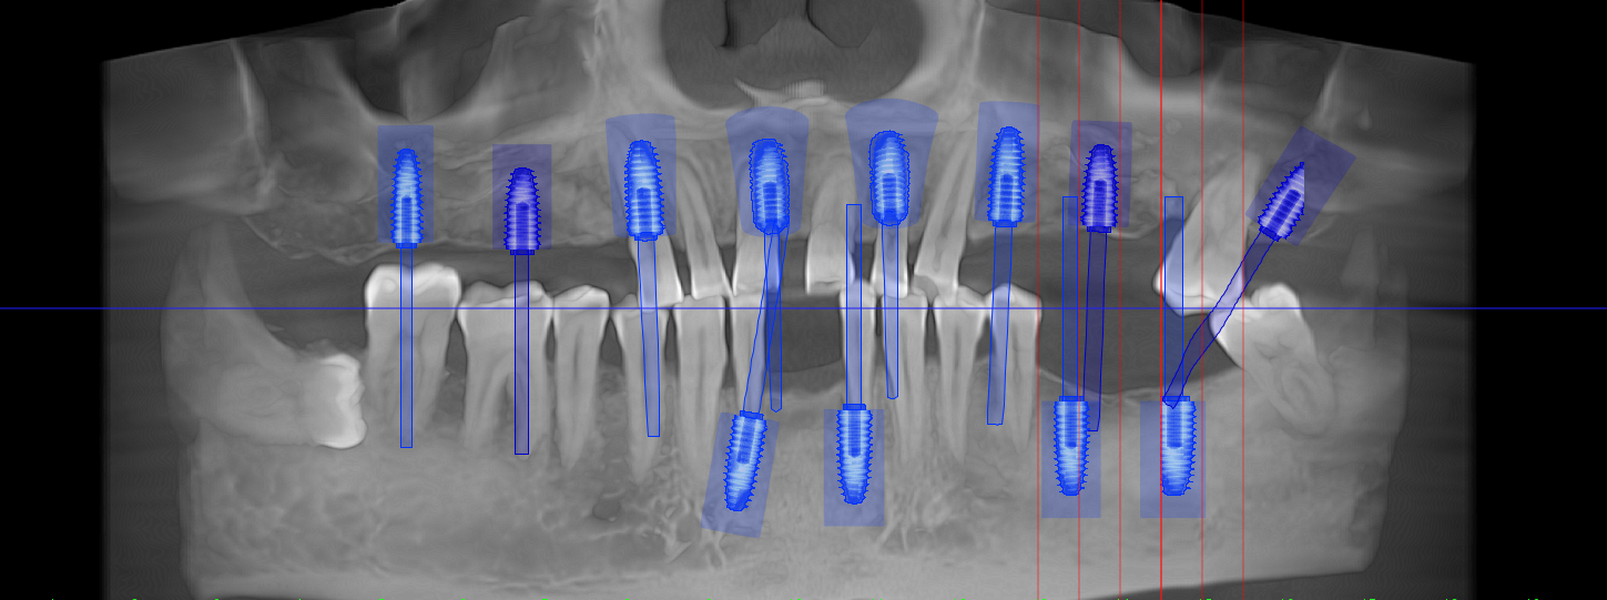

Tomografie (CBCT)

Caz 1